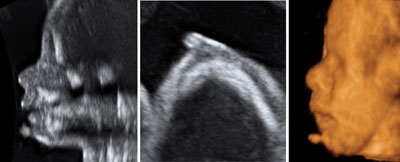

3D sonography of fetal face

Click the image to magnify it

Legend:3D ultrasound is an ideal tool for the evaluation of the fetal face

Reference(s):Merz E, Miric-Tesanic D, Welter C. Value of the electronic scalpel (cut mode) in the evaluation of the fetal face. Ultrasound Obstet Gynecol 2000;16(6):564–8. PubMed PMID: 11169352.

Rotten D, Levaillant JM. Two- and three-dimensional sonographic assessment of the fetal face. 1. A systematic analysis of the normal face. Ultrasound Obstet Gynecol 2004;23(3):224–31. PubMed PMID: 15027008.

Merz E, Benoit B, Blaas HG, Baba K, Kratochwil A, Nelson T, Pretorius D, Jurkovic D, Chang FM, Lee A; ISUOG 3D Focus Group. Standardization of three-dimensional images in obstetrics and gynecology: consensus statement. Ultrasound Obstet Gynecol 2007;29(6):697–703. PubMed PMID: 17523164.